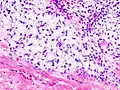

| Histopathologic image of chondrosarcoma of the chest wall. Surgical resection of recurrent mass. H & E stain. | |

Imaging studies – including radiographs ("x-rays"), computerized tomography (CT), and magnetic resonance imaging (MRI) – are often used to make a presumptive diagnosis of chondrosarcoma.[9] However, a definitive diagnosis depends on the identification of malignant cancer cells producing cartilage in a biopsy specimen that has been examined by a pathologist. In a few cases, usually of highly anaplastic tumors, immunohistochemistry (IHC) is required.